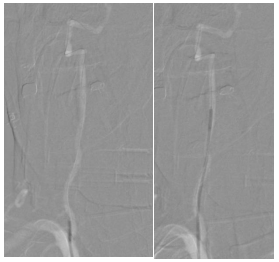

第三步,解除狭窄,恢复血流。选择合适尺寸的球囊扩张式支架,精准释放于右侧椎动脉起始部狭窄段。

第四步,最终验证。再次造影显示:狭窄消失,支架位置良好。动脉瘤不显影,弹簧圈致密填塞。